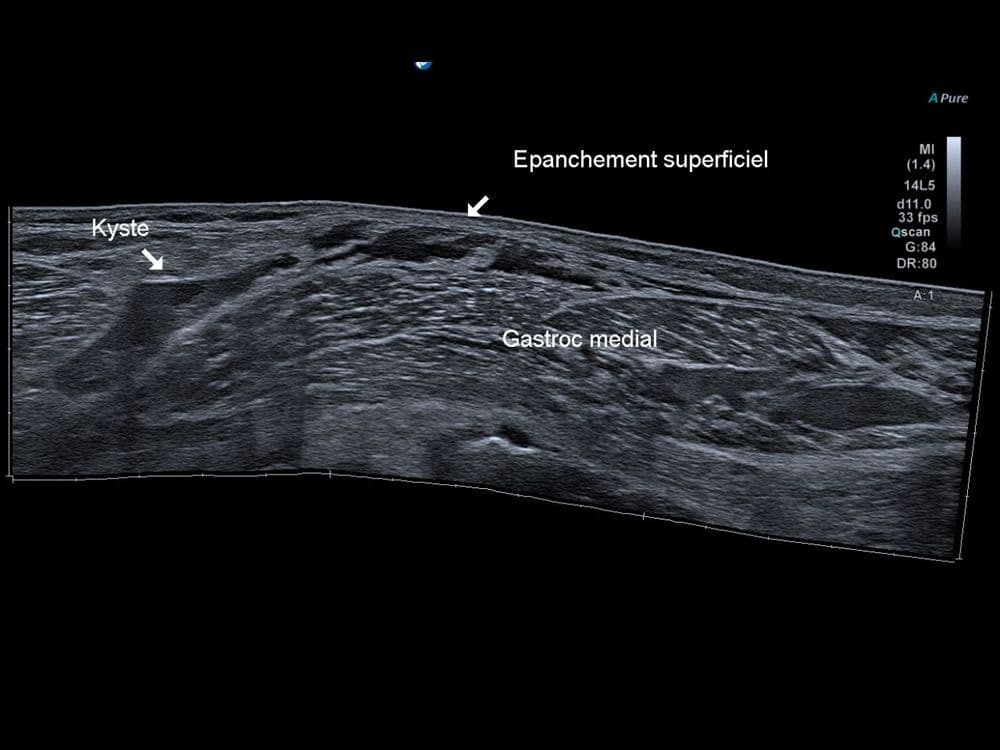

Aspect échographique d'une rupture du kyste poplité de Baker.

US